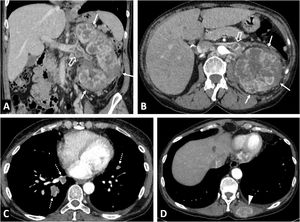

Renal metastasesThe kidney is the eighth most common organ in which metastases occur, with the lung being the most common primary organ. This is seen on imaging in 0.9% of cases (7–20% in autopsies), slightly above the frequency of incidental RCC (0.6%), usually in the context of advanced oncological disease. Although dependent on the primary tumour, growth is generally faster, behaviour tends to be more infiltrative and endophytic, and enhancement is poorer and later than for RCCs42 (Fig. 12).

Renal metastases and mimics. (A) Renal metastases of squamous-cell carcinoma of the lung (arrow), exhibiting multiple renal masses with poor enhancement and infiltrative behaviour (*). (B) Renal metastases of adenocarcinoma of the gallbladder with extensive infiltration of the adjacent liver parenchyma (arrows) and extensive peritoneal carcinomatosis, also within an inguinal hernia (hollow arrows). The renal lesions (*) behave similarly to the primary neoplasm, with moderately intense and heterogeneous enhancement, and abundant tumour necrosis. In this case, the lesions have a more expansive behaviour. (C) Clear cell renal cell carcinoma mimicking breast carcinoma metastasis in a 64-year-old woman undergoing oncological follow-up due to her medical history. Exophytic, expansive renal cortical lesion with enhancement almost as intense as that of the parenchyma (arrows). A retrospective review of previous studies showed that it was present in a study performed two years earlier (dashed arrow), with slower growth than expected for metastasis. The diagnosis was confirmed following percutaneous biopsy and tumour removal. (D) Contralateral renal metastases of clear cell carcinoma (ccRCC) or Von Hippel-Lindau? An 82-year-old female underwent a right nephrectomy for ccRCC. CT images show numerous markedly enhancing contralateral renal nodules with cystic appearance and thick walls, which is the usual appearance of lesions in Von Hippel-Lindau syndrome. However, hypervascular metastases coexisted in both the left adrenal region (arrowhead) and lung (not shown). The patient died without a confirmatory genetic diagnosis.

Lymphomas, usually of the B-cell non-Hodgkin variety, have renal involvement that has been radiologically confirmed in 1–8% of cases (30–60% in autopsies). They are usually bilateral and involve lymph node and/or other organ disease. In the literature, diffuse infiltration is the most common histological pattern, and imaging reports most frequently describe multifocal lesions.43 In our experience, perirenal infiltration is the most common pattern, often extending into the renal sinus. The lesions are infiltrative, homogeneous and hypoenhancing with marked diffusion restriction (Fig. 13). Similar findings are seen in certain types of leukaemia.

Renal lymphoma. (A) Diffuse infiltration of both kidneys (arrows), in addition to infiltration also demonstrated by a lymphoma of the prostate (+), with the stem of a bladder catheter in its urethral section, and a lymphoma of the gastric wall (*). (B) Multiple and bilateral nodules with discrete enhancement (*). (C) Perirenal solid masses (*) with discrete enhancement, which infiltrate the superficial renal parenchyma (arrows) and penetrate the renal sinus (+), causing discrete hydronephrosis (arrowheads), albeit sparing the vessels (not shown). (D) Peripelvic and renal sinus infiltration (*), in this case accompanied by abundant retroperitoneal and mesenteric lymphadenopathies (+). (E) Infiltration of the renal sinus, with significant water diffusion restriction, high signal in the diffusion sequence with B = 800 s/m2 and low signal in the apparent diffusion coefficient (ADC) map (arrows).